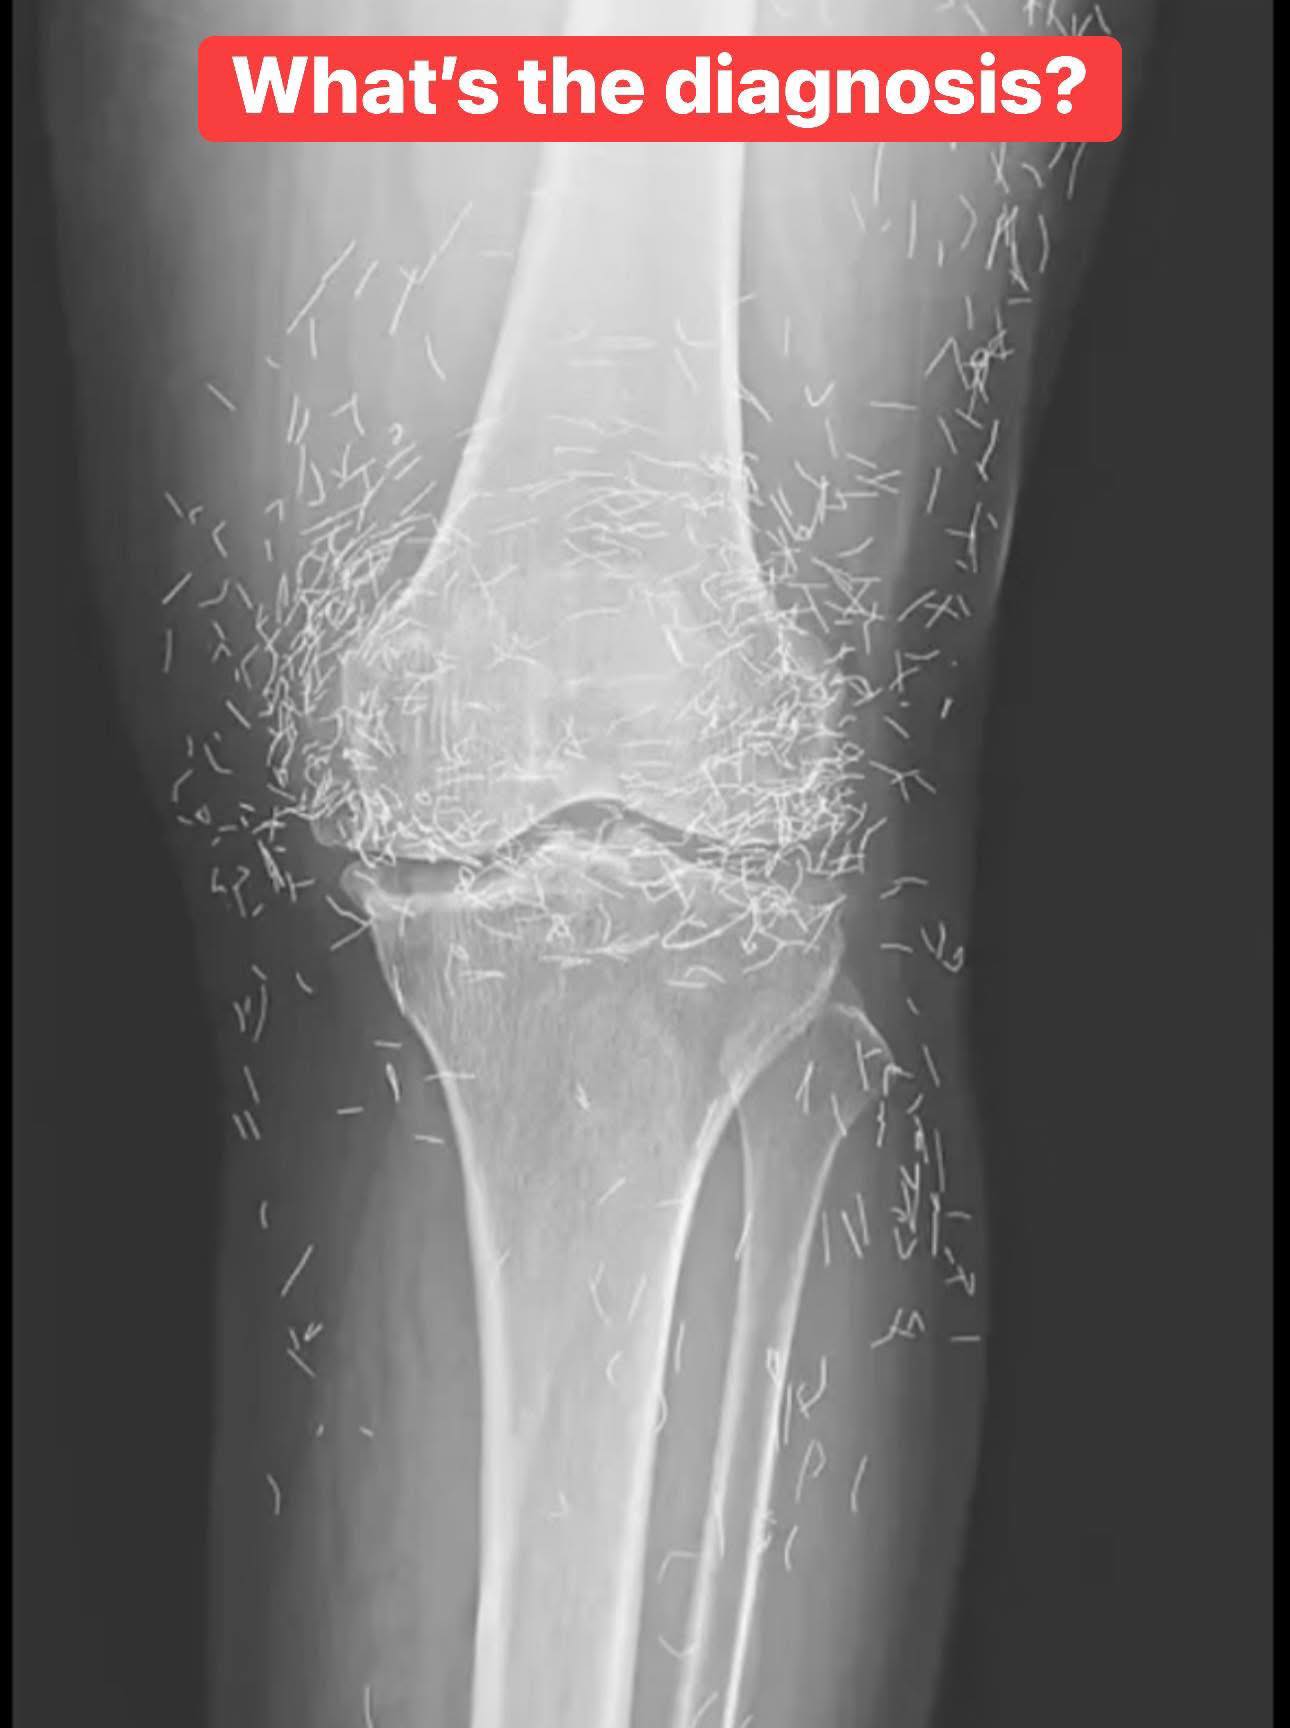

Doctors find “gold mine” in woman’s knees

When a 65-year-old South Korean woman went in for knee pain, doctors weren’t expecting to strike gold. But that’s exactly what they found. Unwanted stomach issues Living with osteoarthritis can be incredibly challenging. The condition gradually wears down the cartilage in your joints, leading to stiffness, swelling, and persistent pain that can make even simple … Read more